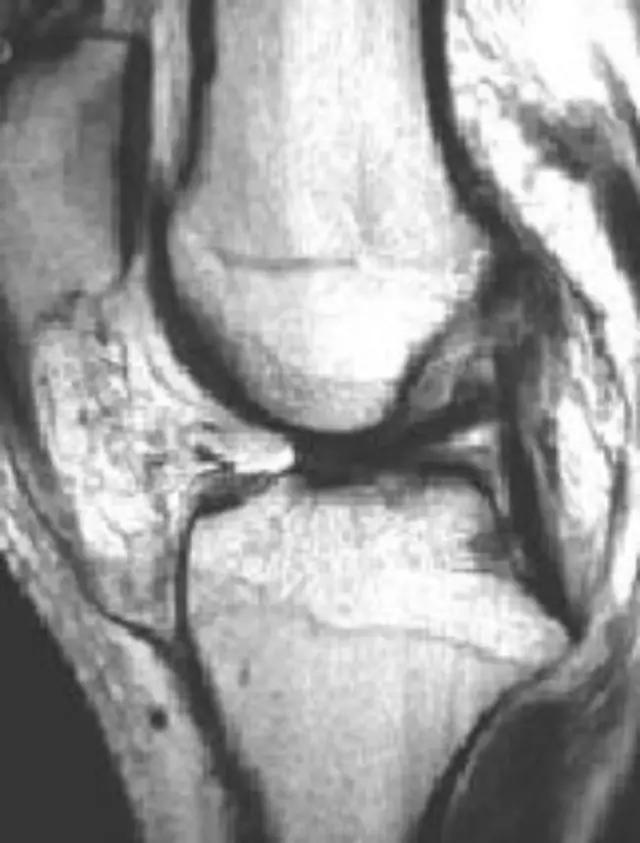

病例:游XX,男,67岁,右膝肿胀活动困难伴进行性畸形6年。疼痛不重!下图为2010年照片,DR和MR显示胫骨内侧平台骨缺损,无其他病变,很难确诊。

利用疾病发展——

下图为2014年DR,显示关节破坏严重,但疼痛不重,符合神经性关节炎的疾病特点:关节破坏极度严重,临床症状轻微!